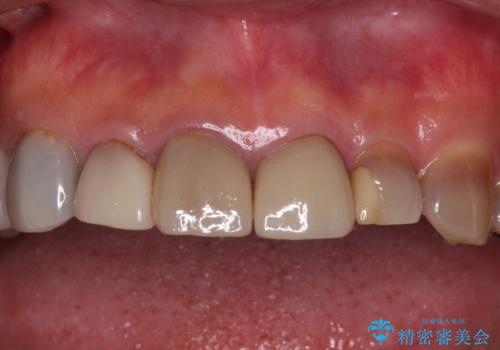

- 前歯のテトラサイクリンによる変色歯と、レジン充填の色の違いを気にして来院された患者様です。

患者様の希望により、前歯6歯をオールセラミッククラウンにて補綴することとしました。